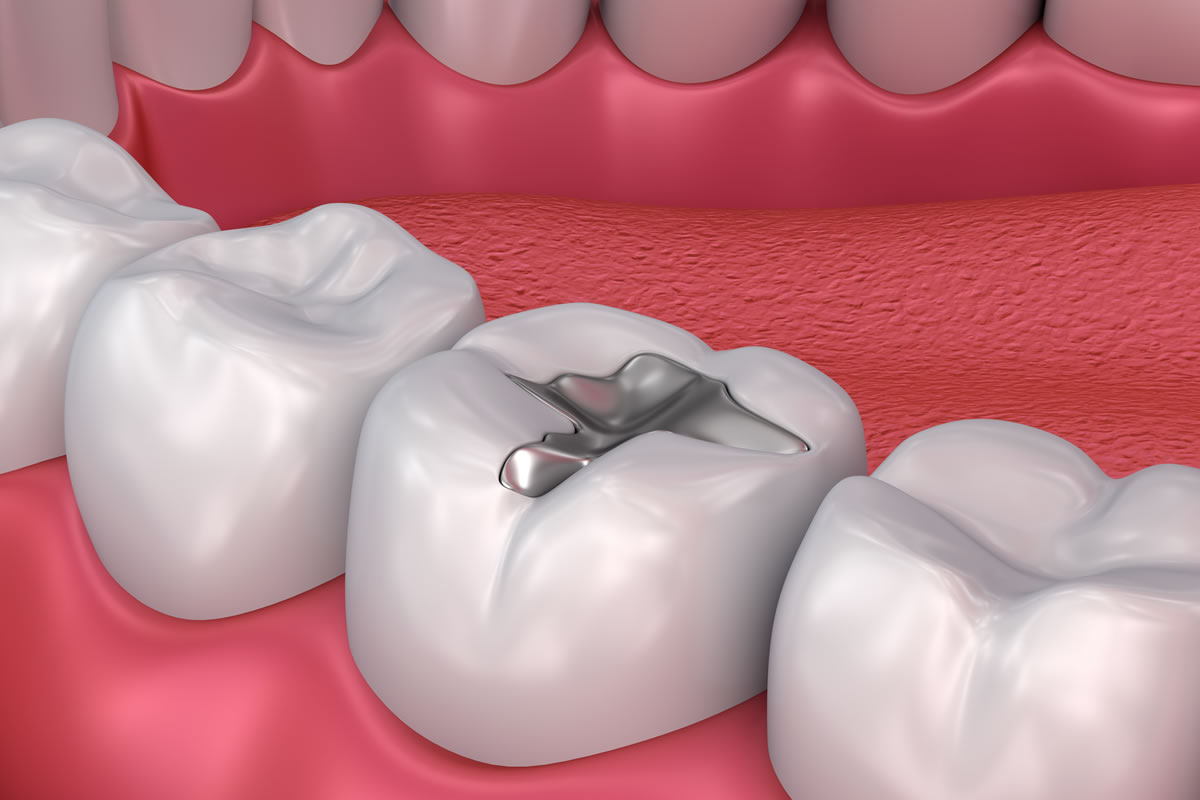

ما الفرق بين الحشوات الفضية والبيضاء؟

كلتا المادتين قابلة للمقارنة الآن في طول العمر والقوة. الفرق في فمك هو المظهر التجميلي (الجماليات). في الحالات التي يكون فيها التجويف صغيرًا ، قد يكون الحشو الملون للسن اللاصق هو الخيار الأمثل ، ولكن يمكن أيضًا استخدامه في التجاويف المتوسطة الحجم في الأسنان الأمامية أو الخلفية. حشوات الملغم (الفضة) مناسبة للتجاويف المتوسطة والكبيرة الحجم. إذا كنت تفضل حشوًا ملونًا للأسنان في تجويف أكبر ، فقد ينصحك طبيب الأسنان بالتفكير في حشوة / حشوة.

تتوفر الحشوات بالفضة المكونة من الزئبق والفضة والقصدير ومعادن أخرى تعرف بالملغم. لا يلتصق الملغم بالأسنان أو يلتصق بها ويعتمد على الاحتفاظ الميكانيكي لتثبيت الحشو. الحشوات البيضاء (الحشوات الملونة للأسنان) هي مادة حديثة للأسنان ويمكن أن تلتصق بمادة الأسنان وتتوافق مع لون أسنانك وملمسها وشكلها

حشوات الملغم (الفضة) مقاومة للتآكل وغير مكلفة نسبيًا. ومع ذلك ، وبسبب لونها الغامق ، فهي أكثر وضوحًا من الترميمات المصنوعة من البورسلين أو المركب ولا تُستخدم عادةً في المناطق المرئية جدًا ، مثل الأسنان الأمامية.

لسنوات عديدة ، كان وضع الملغم (الحشوات الفضية) في تجاويف / ثقوب الأسنان أمرًا شائعًا ، ونتيجة لذلك ، فإن العديد منا قد تغير لون أسنانه بسبب حشوات الملغم. في السنوات الأخيرة ، تم التركيز على إعادة أسناننا إلى حالتها الطبيعية ، وتغيير هذه الحشوات إلى ترميمات جديدة بلون الأسنان.

هنا في مركز لؤلؤة الخليج للأسنان ، فإن إزالة حشوات الملغم القديمة لترميم الأسنان التجميلية الجديدة هي حل بسيط لتحسين ابتسامتك. غالبًا ما تعطي حشوات الملغم الأسنان مظهرًا رماديًا مما يجعل الابتسامة داكنة. إذا كنت قد حافظت على ابتسامة صحية لسنوات عديدة ، ولم يكن لديك حشوات ملغم ، فإن حشوة بيضاء اللون ستضمن بقاء جماليات ابتسامتك في أفضل حالاتها